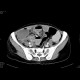

Large masses in the region of both ovaries, right-sided hydronephrosis

Radiology image - Krukenberg tumor, ovarian metastases from stomach tumour, hydronephrosis: Abdomen, Gynecology, Stomach, Urinary tract: CT - Computed tomography

Krukenberg tumor, ovarian metastases from stomach tumour, hydronephrosis